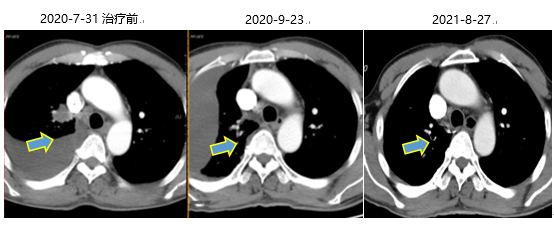

2020年7月31日

胸部CT:上叶纵隔旁见结节灶,大小2.9cm×2.2cm×2.9cm,双肺弥漫多发粟粒结节灶,大小不等。纵隔内(2R、4R、4L区)多发肿大淋巴结,较大者短径约1.0cm。右侧胸腔积液。

图片YkT帝国网站管理系统

胸部CT提示:口服阿美替尼2个月后,原双肺弥漫粟粒结节灶已明显减少、缩小;纵隔淋巴结转移较之前好转;双肺多发转移较前好转。8月26日末次随访时右肺上叶纵隔旁见少许不规则软组织密度结节影,双肺磨玻璃结节直径不足0.5cm,纵隔及肺门未见肿大淋巴结。YkT帝国网站管理系统